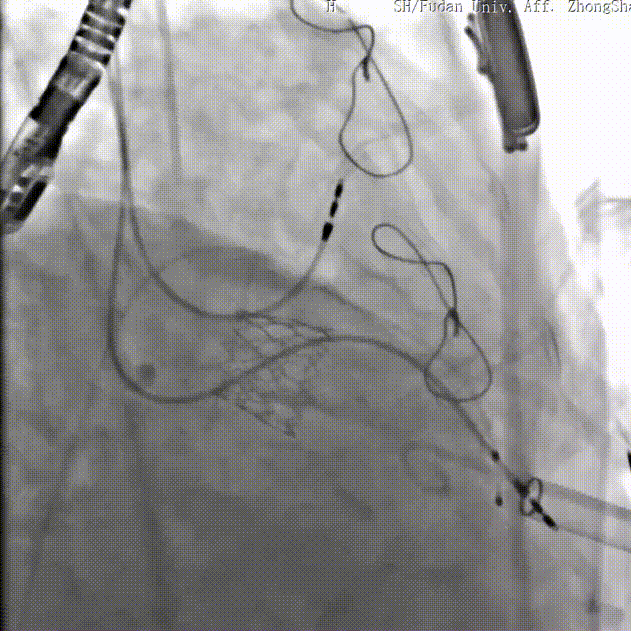

三尖瓣病例:

患者女性,62岁,既往三尖瓣位植入29# SAV猪瓣,超声提示三尖瓣人工瓣膜衰败,压差升高伴重度关闭不全。患者合并房颤伴长间歇、巨大右房、右心功能差,经独立专家委员会评判该患者属于外科手术高风险。术前经详尽影像学测量及多学科讨论,反复模拟分别经股静脉及经颈静脉入路输送瓣中瓣至三尖瓣的角度后,发现经右侧颈静脉入路瓣膜输送角度更理想。

手术顺利,经右颈静脉入路成功植入27号Renato球扩式瓣中瓣。瓣膜植入位置理想,无瓣周漏及中央返流。经查阅现有资料,经颈静脉路径成功完成三尖瓣“瓣中瓣”治疗在国内尚属首例。

▲球扩三尖瓣 ▲右室造影